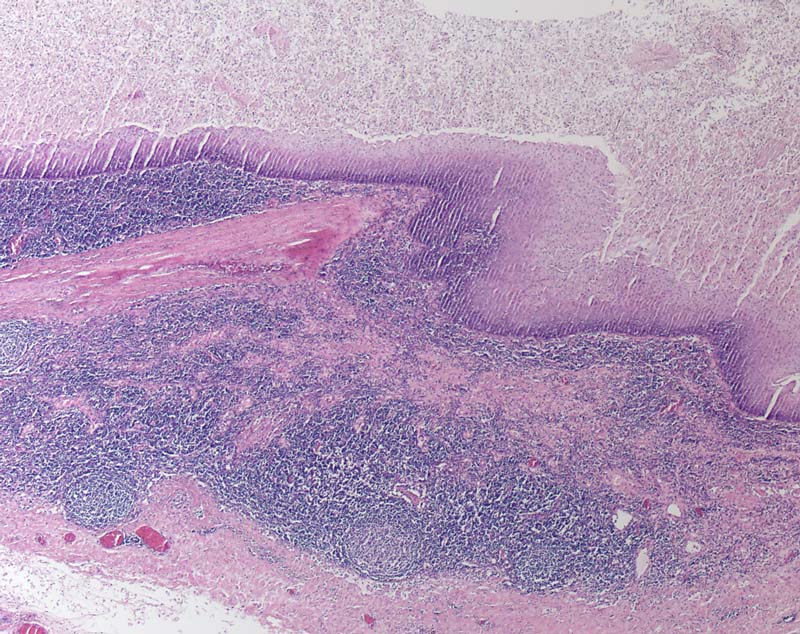

Branchiogene Zyste

Auskleidung der Zyste durch mehrschichtiges Plattenepithel. Dichtes lymphozytäres Infiltrat mit Keimzentren in der Zystenwand.

Laterale Halszyste.

Embryonale Fehlbildung der Kiemenbogenfurchen. Zyste oder Fistel in Halsmitte, am Vorderrand des Sternocleidomastoideus oder präaurikulär. Auskleidung meist durch Plattenepithel, seltener durch Flimmerepithel. Dichtes lymphozytäres Infiltrat in der Zystenwand im Gegensatz zur bronchogenen Zyste.

Histologie

25